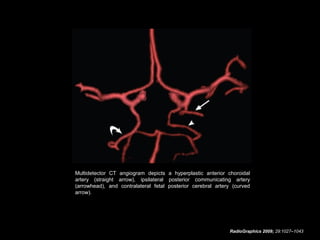

Hyperplastic Anterior

Choroidal Artery

• The anterior choroidal artery, usually a small vessel,

arises from the supraclinoid internal carotid artery just

distal to the posterior communicating artery.

• From there it subdivides into important branches that

supply the cerebral peduncle and optic tract.

• The temporo-occipital branches of the posterior cerebral

artery may arise from the anterior choroidal artery.

• In people with this cerebrovascular variant, the anterior

choroidal artery is described as hyperplastic.

• The prevalence of hyperplastic anterior choroidal arteries

is reported to be 1.1%–2.3%.

RadioGraphics 2009; 29:1027–1043

Multidetector CT angiogram depicts a hyperplastic anterior choroidal

artery (straight arrow), ipsilateral posterior communicating artery

(arrowhead), and contralateral fetal posterior cerebral artery (curved

arrow).